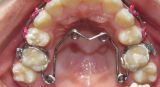

Съемные ортодонтические аппараты

Высококачественные ортодонтические съемные аппараты, которые помогают решить различные ортодонтические проблемы с максимальным комфортом и эффективностью.